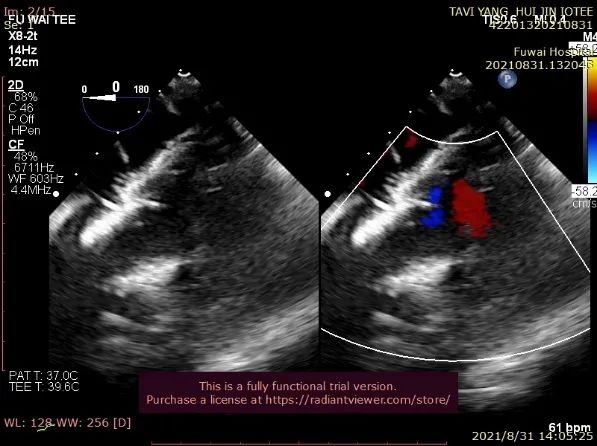

术后即刻放射线显示人工瓣膜位置良好,随心跳运动,与周围组织无相对位移;TEE显示人工主动脉瓣金属支架位置良好,瓣环下支架长度约7mm,支架自膨后外径为26.8mm,接近瓣膜真实外径(图6),CDFI多角度观察,舒张期冠脉开口处血流通畅,左室流出道侧人工瓣和自体瓣环之间仅见微量反流信号(图7),收缩期人工瓣口流速良好(峰值流速:2.0m/s,峰值压差:17mmHg)(图8)。

图7. TEE提示做冠脉开口处血流通畅,无冠窦和左冠窦交界处可见微量瓣周漏